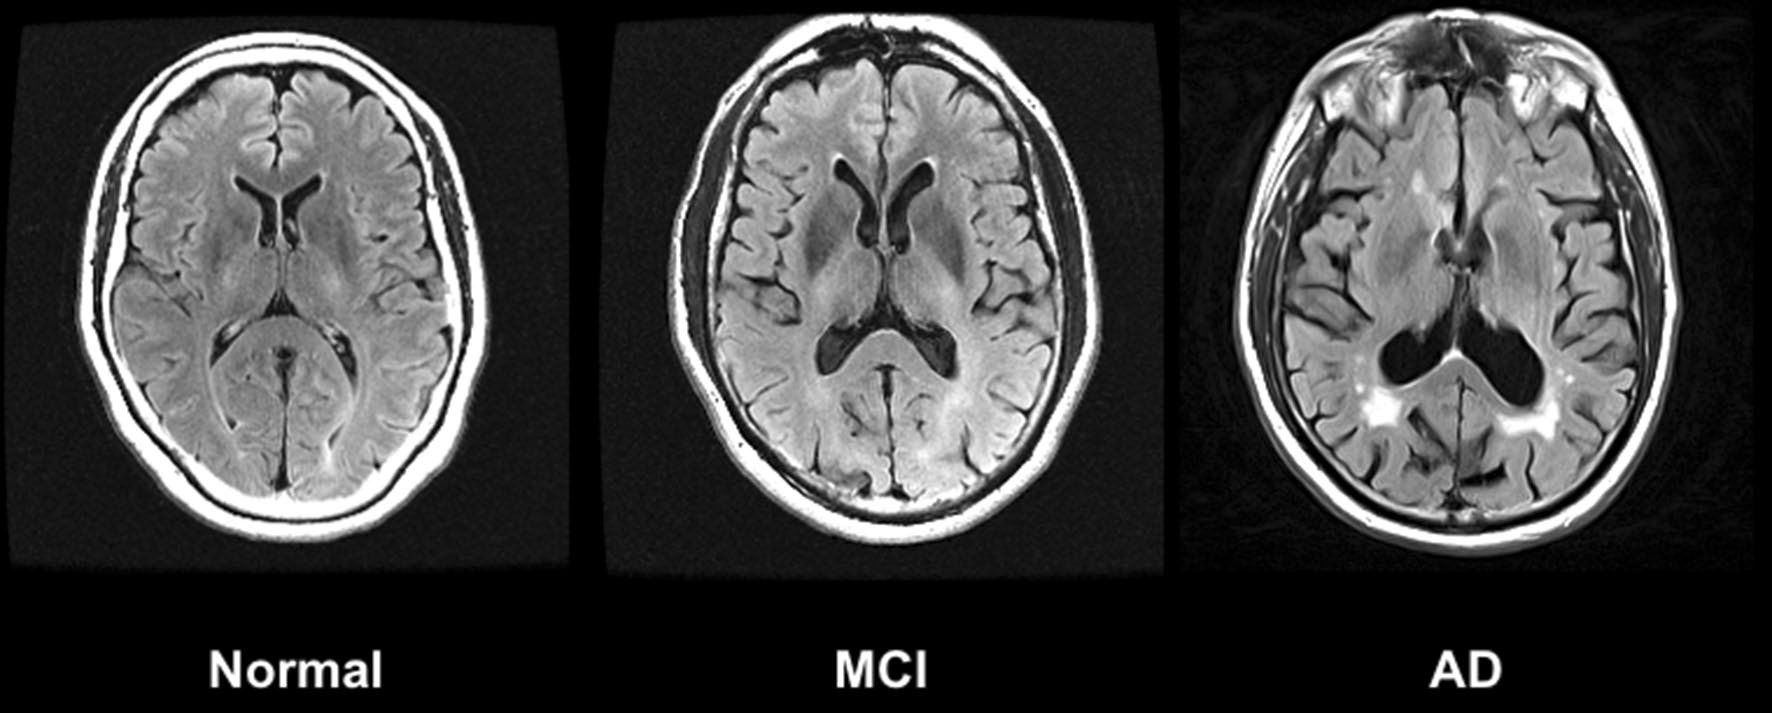

Wichtig ist dabei eine klare Unterscheidung: Von einer leichten kognitiven Beeinträchtigung (Mild Cognitive Impairment, MCI) spricht man, wenn geistige Leistungen messbar nachlassen, der Alltag jedoch noch weitgehend selbstständig bewältigt wird. Demenz bezeichnet hingegen keinen einzelnen Krankheitsverlauf, sondern einen Zustand mit anhaltenden und im täglichen Leben spürbaren Leistungseinbussen in mehreren geistigen Bereichen, vor allem im höheren Lebensalter. Alzheimer wiederum ist die häufigste Ursache einer solchen Demenzform – eine eigenständige Erkrankung, bei der es zu strukturellen Veränderungen im Gehirn kommt und Nervenzellen zunehmend geschädigt werden.